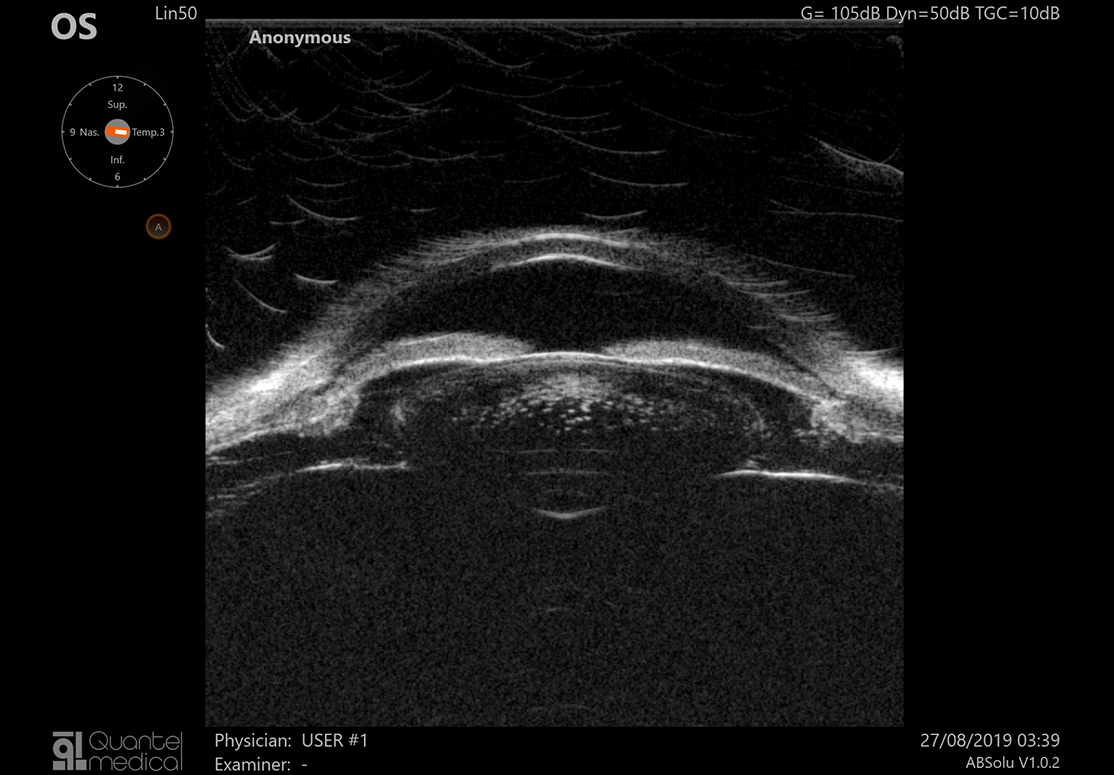

ABSolu prichádza s novým typom 20 Mhz B-sondy, pozostávajúcej z piatich snímačov rôznych priemerov, ktorá zvyšuje hĺbku poľa o 70% a laterálne rozlíšenie o 27%. To umožňuje simultánne vyšetriť patológie sklovca, sietnice a orbity bez ústupkov na kvalite snímky. Štandardizovaná sonda zas zabezpečuje diagnostiku tumorov, odlúpenia sietnice, či Gravesovej choroby. Sondy B15 a B20 obsahujú senzor, ktorý automaticky zisťuje a v reálnom čase znázorňuje polohu sondy a smer lúča.

- väčšia hĺbka ostrosti umožňujúca vizualizáciu celého oka,

- vynikajúce rozlíšenie od prednej časti sklovca až k stenu,